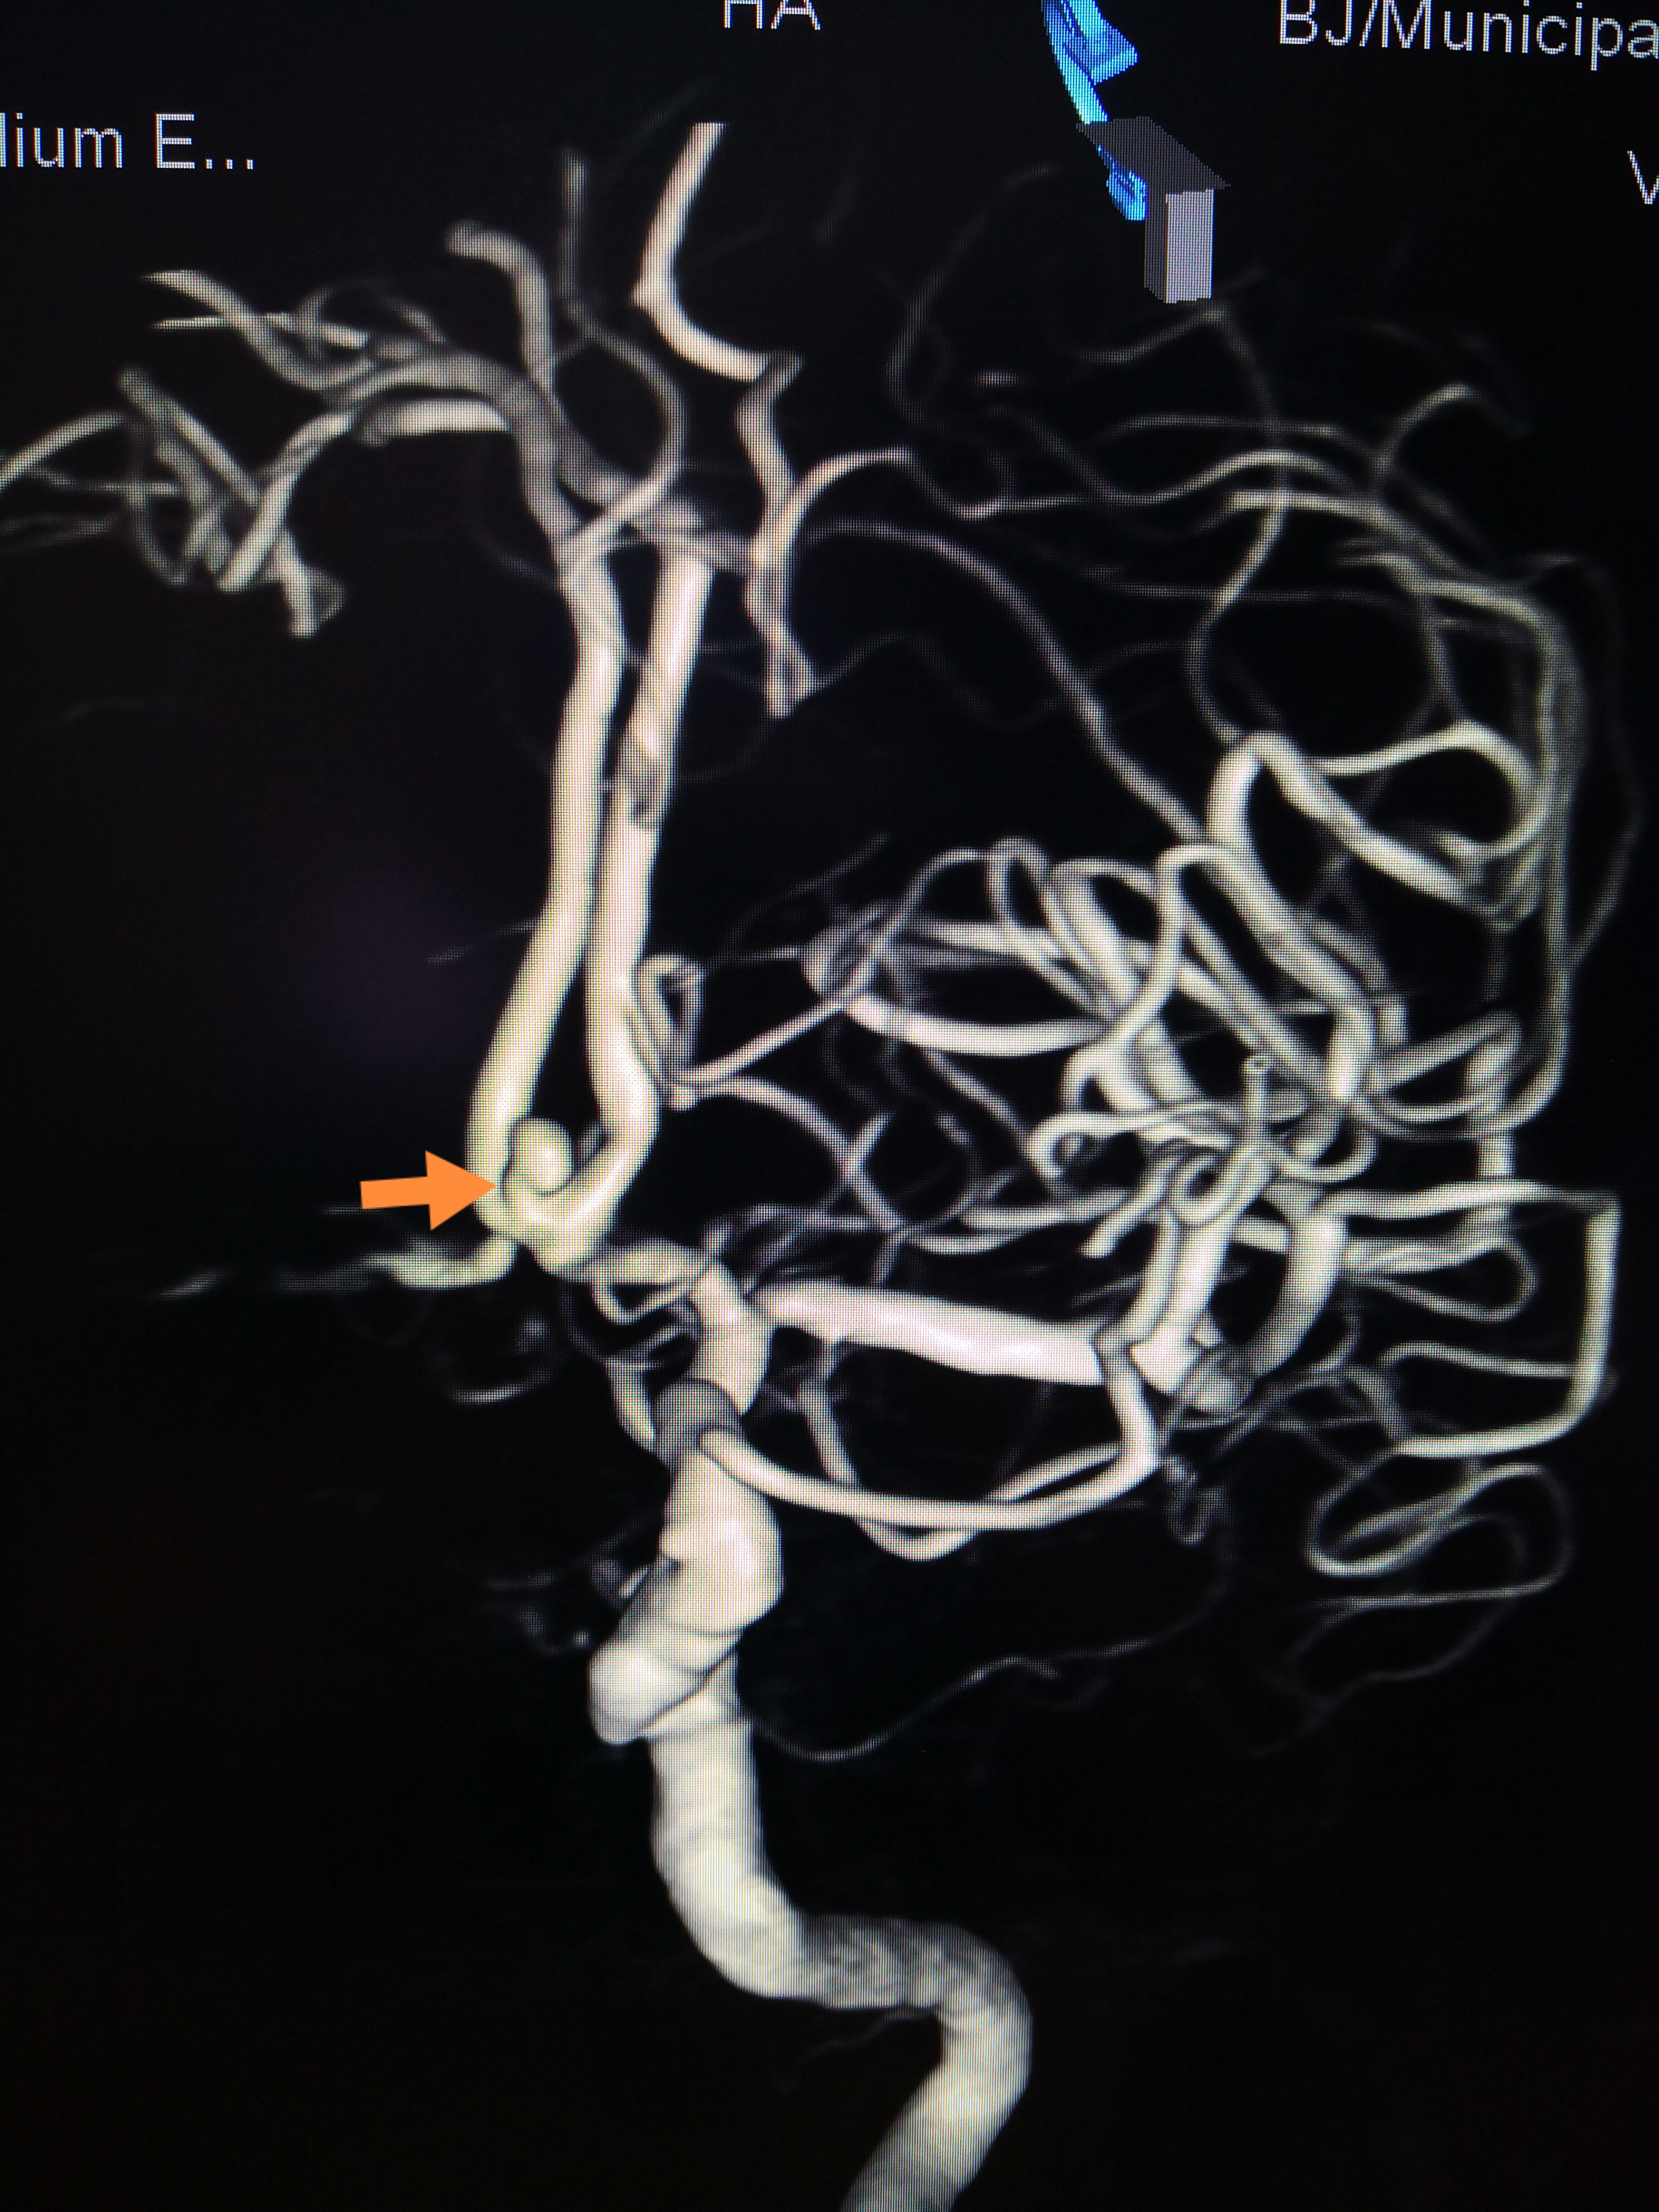

手术前后对比,动脉瘤致密栓塞,载瘤动脉通畅

7月9日,在导管室、麻醉科的全力配合下,由神经外科脑血管病介入团队在全麻下实施了前交通动脉瘤弹簧圈栓塞术。手术中,神经外科介入团队沉稳操作,克服了严重头颈动脉粥样硬化及迂曲的困难,一步步精准操作将中间导管送达指定位置,栓塞微导管小心进入动脉瘤,栓塞弹簧圈缓慢送入动脉瘤腔内。经过2个小时的手术,患者这颗颅内“不定时炸弹”被成功拆除。过程顺利,动脉瘤达到致密栓塞,载瘤动脉通畅。术后第一天为患者实施了腰大池置管,引流血性脑脊液。术后第二天患者神志转清,拔除气管插管,目前正在进一步治疗中。患者家属由衷的表示感谢,特意写了感谢信。